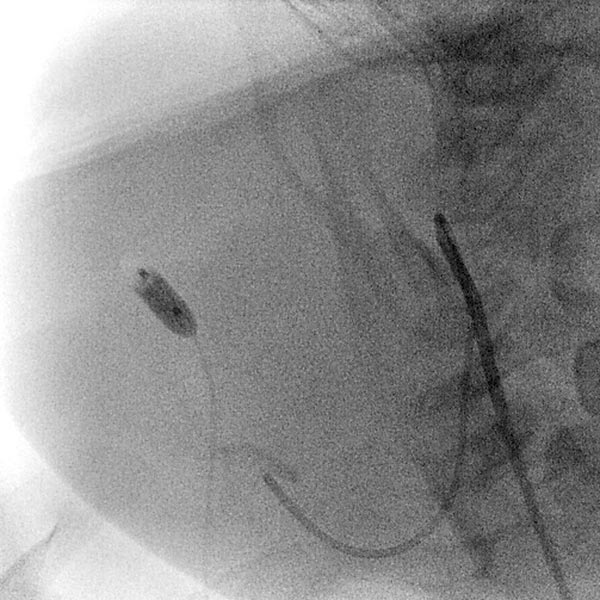

Das Mädchen ist jetzt 24 Monate alt, die Raumforderung hat sich nicht zurückgebildet. Sie ist deutlich sichtbar und bereitet der Patientin klaren Druckschmerz. Die MIP einer dynamischen, kontrastmittelunterstützten MR-Angiographie zeigt die starke Anreicherung des Hämangioms, das immer noch ausgedehnt ist. Die hauptsächliche venöse Drainage läuft über die Vena jugularis externa, im proximalen Bereich zeigt sich hier eine massive Stenose des Abstroms.

Aufgrund der fehlenden Rückbildung, wahrscheinlich auch durch die massive Stenose des venösen Abstroms, fällt der Entschluss zur Embolisation des Hämangioms im 24. Lebensmonat zur Induktion einer Regression. Zunächst wird dazu retrograd von transvenös der venöse Abstrom (Vena jugularis externa rechts) kanüliert.